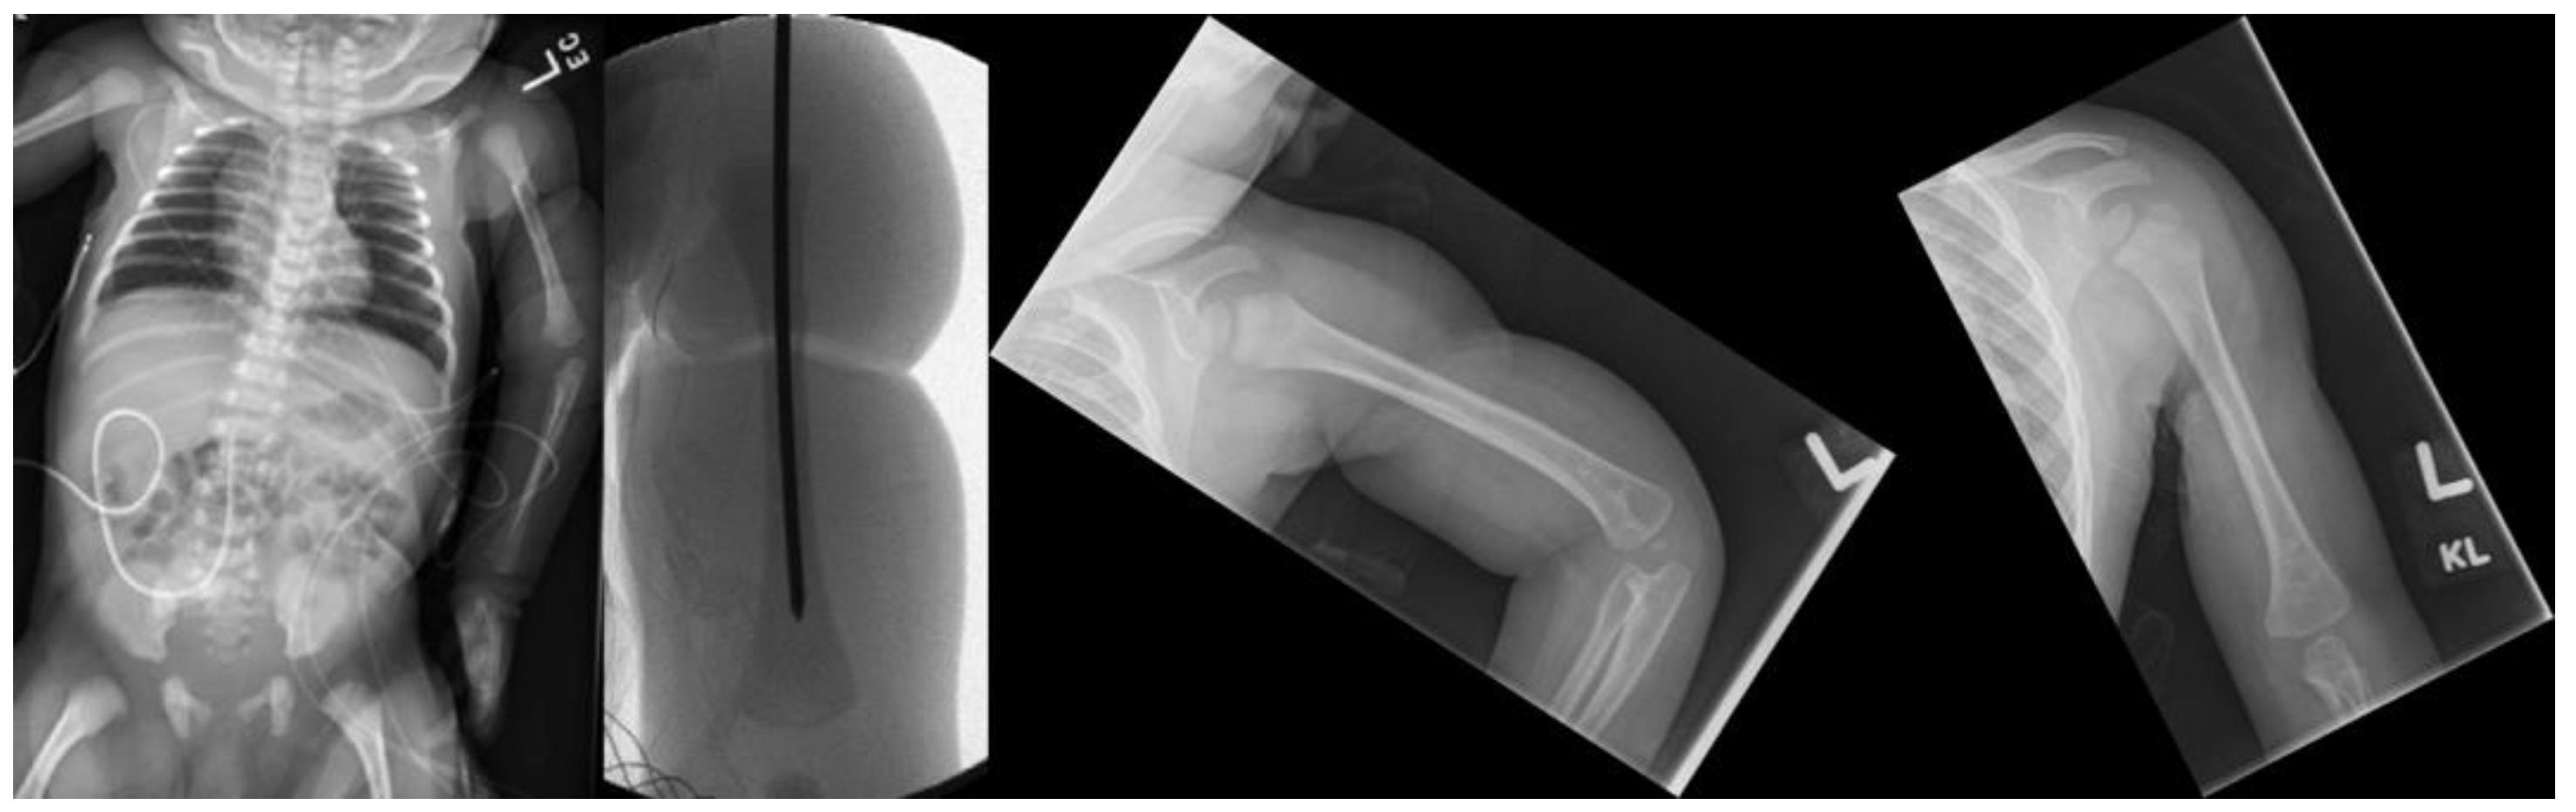

Fractures in the Setting of Constriction Band Syndrome: A Case Series of Three Patients with Extremity Fractures at the Site of a Constriction Band

2. Case Presentation